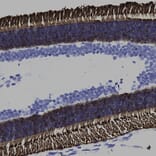

Immunohistochemistry analysis of a 4% PFA fixed paraffin embedded rat retina section with Anti-Rhodopsin Antibody [B630] (A85373) at a dilution of 1:2,000. Anti-Rhodopsin Antibody [B630] (A85373) strongly labels the rod cells within the photo receptor layer of the retina. Note: Note: this antibody has not been tested in NBF fixed material.